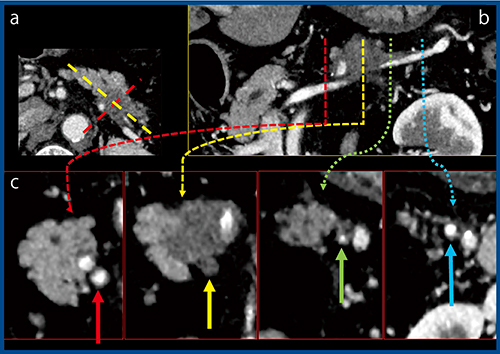

症例1は膵尾部がんだが,Aquilion Precisionでは従来CTとの比較で画像がよりシャープになっており,腫瘍の範囲などを評価しやすくなっている(図1)。また,Aquilion Precisionでは病変部の確認だけでなく,脾動脈および脾静脈への浸潤まで確信を持って診断できる。図2 cの斜矢状断像では,脾静脈は開存(↑)しているが,血管の内腔まで腫瘍が充満(↑)しており,さらに一部開存した部分(↑)やしっかりと開存している部分(↑)など,腫瘍と血管の位置関係がクリアに描出され,病理所見とも一致した。

図2 症例1:膵尾部がん(Aquilion Precision)

a:横断像 b:脾静脈の斜冠状断画像 c:同斜矢状断像